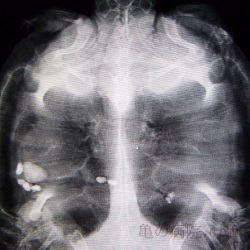

3診断

レントゲンや超音波で診断する

消化管内に金属部分を含む異物。

洗濯ばさみ?

水槽内の小石